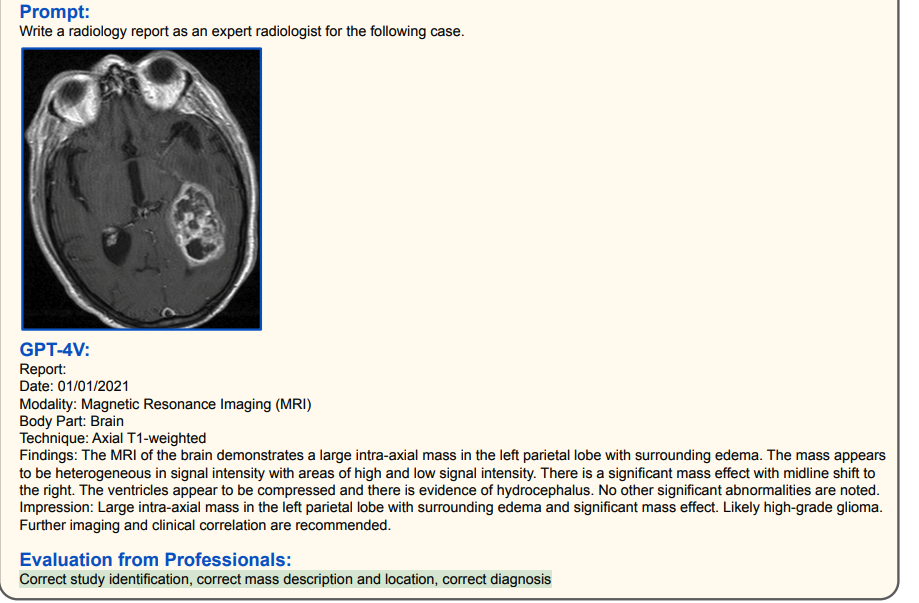

1.2 医学诊断(高准确率)

其他脑部/胸部X光诊断(高准确率)

(绿色代表正确,红色代表错误,黄色代表幻觉)